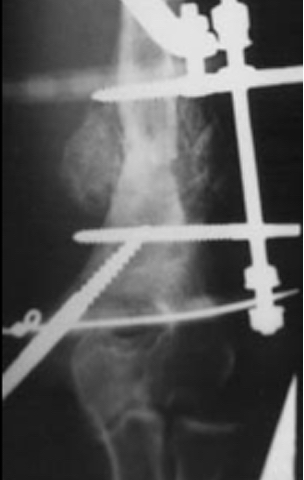

3. Defekt Psödoartrozlar

Genellikle birden çok kez cerrahi müdahele geçirmiş ya da osteomiyelitise bağlı kemik rezeksiyonu nedeniyle, çok nadiren de tümör rezeksiyonuna bağlı oluşmuş defektlerdir. Bilindiği gibi humerus da oluşan kısalık kimi otörlere göre 4cm bazılarına göre de 6 cm’ye kadar fonksiyonel bir yetersizlik ortaya çıkarmaz. Segment transportu monofokal osteogeneze göre daha komplike olduğundan 4-6 cm ‘lik defektler kadar psödoartroz mobil psödoartroz olarak kabul edilmelidir. Bunun üzerindeki defektlerde konvansiyonel olarak damarlı fibula grefti ya da allogreft uygulamalarının yanında, İlizarov’a göre segment transportu da bir tedavi seçeneğidir. Tümör rezeksiyonları dışındaki defektler genellikle 7 cm’nin altında olduğundan ( 4 cm kabul edilebilir defekt + 3 cm ilave kemik defekti) uygulanan teknik eksternal segment kaydırma olmalıdır. Bifokal osteogenezis olarak da isimlendirilen tedavinin süresini kısaltmak için önerilen bir yöntem de akut kısaltma ve tedrici uzatmadır. Aslında segment transporttan prensipte farklı olmayan bu uygulamada, hedef bölgenin kaynaması için geçen süre esnasında ekstremite uzatılacaktır.